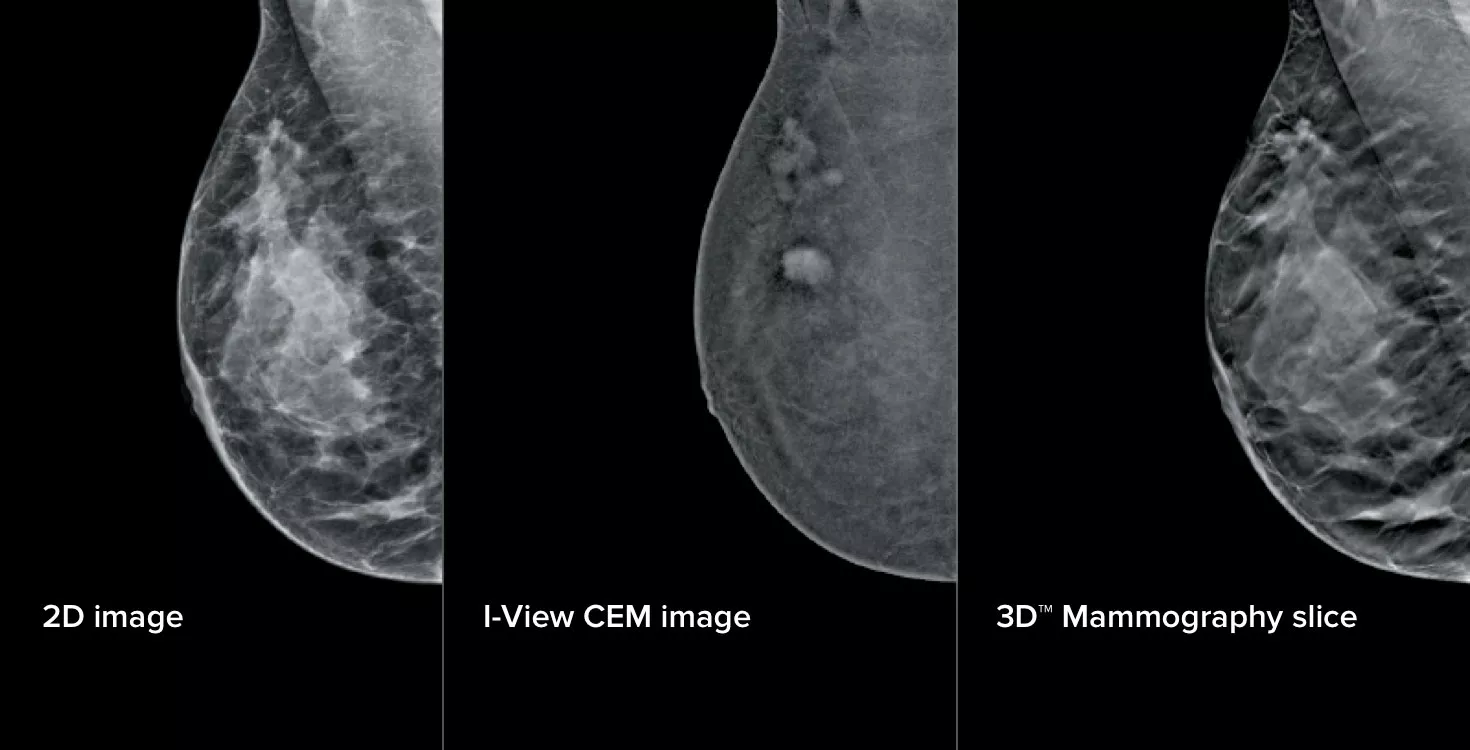

Kontrastforbedret mammografi (CEM) – billeddannelse af et bryst ved hjælp af jodholdig kontrast for at afsløre områder med øget blodforsyning i brystet – kan bidrage til at fremhæve mistænkelige læsioner. I-View-softwaren kan kombinere styrken i CEM med 2D- og tomosyntesebilleder, alt sammen under én kompression, hvilket giver anatomisk og funktionel billeddannelse i én undersøgelse.1

3 billeder fra 1 kompression

Denne software registrerer både anatomiske og funktionelle oplysninger i en enkelt undersøgelse ved at udnytte vores evne til at levere 2D-, kontrast- og tomosyntesebilleder i blot én kompression.1